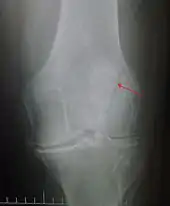

The patella can break in various ways depending on the way it is injured, and into two or more pieces.[1] Types include transverse, with one fracture line and is the most common type,[5] marginal, osteochondral and the rare vertical type, or stellate, where a direct compression force gives rise to a comminuted pattern.[5][7] Patella fractures can be further classified as displaced, where the broken ends of bone do not line up correctly and separate by more than 2mm, or undisplaced and stable where pieces of bone remain in contact with each other.[1][7] If fragments of patella bone stick out from the skin it is known as an open patella fracture, and closed if the overlying skin is intact.[1]

Transverse fracture of patella